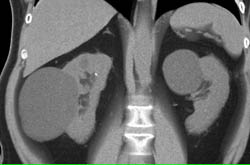

Complex Right Renal Cyst With Calcification